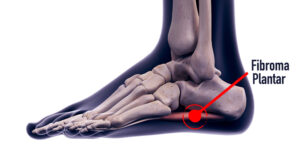

El fibroma plantar es un nódulo benigno que se forma en la fascia plantar, una banda gruesa de tejido conectivo que proporciona soporte al arco del pie. Este bulto suele ser de crecimiento lento, aunque en algunos casos puede aumentar de tamaño con el tiempo.

En general se pueden diagnosticar mediante la exploración clínica y una correcta anamnesis. A su vez nos apoyaremos en ecografías o RMN para visualizar la masa fusiforme, delimitar el grosor y diferenciar estructuras afectadas. A nivel de la zona dolorosa se puede apreciar una formación fusiforme de 15 mm hipoecogénica adyacente a la fascia plantar.

El síntoma principal del fibroma plantar es la presencia de un bulto palpable en el arco del pie. En las primeras etapas, este nódulo puede ser pequeño y no causar molestias. Sin embargo, a medida que crece o si está ubicado en una zona de apoyo, puede generar dolor en el arco plantar y rigidez en la fascia plantar.